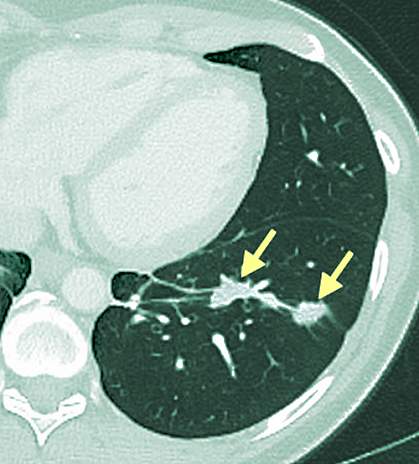

A 43-year-old woman with cholangiocarcinoma, a cancer that develops in the bile duct, was enrolled in an NIH clinical trial for patients with gastrointestinal cancers. Her cancer had spread to her lung and liver and hadn’t responded to standard chemotherapy.

Following transfer of the TILs, the woman’s metastatic lung and liver tumors stabilized. When her disease eventually progressed, after about 13 months, she was re-treated with a 95% pure population of mutation-reactive T cells. After this treatment, she experienced tumor regression that was ongoing as of the last follow-up 6 months later.